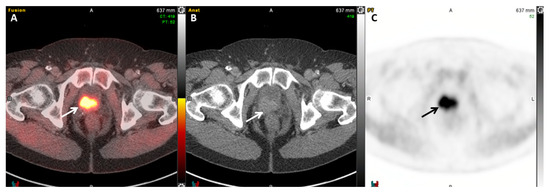

- Rowe, S.P.; Macura, K.J.; Mena, E.; Blackford, A.L.; Nadal, R.; Antonarakis, E.S.; Eisenberger, M.; Carducci, M.; Fan, H.; Dannals, R.F.; et al. PSMA-Based [18F]DCFPyL PET/CT Is Superior to Conventional Imaging for Lesion Detection in Patients with Metastatic Prostate Cancer. Mol. Imaging Biol. 2016, 18, 411–419. [Google Scholar] [CrossRef] [PubMed]